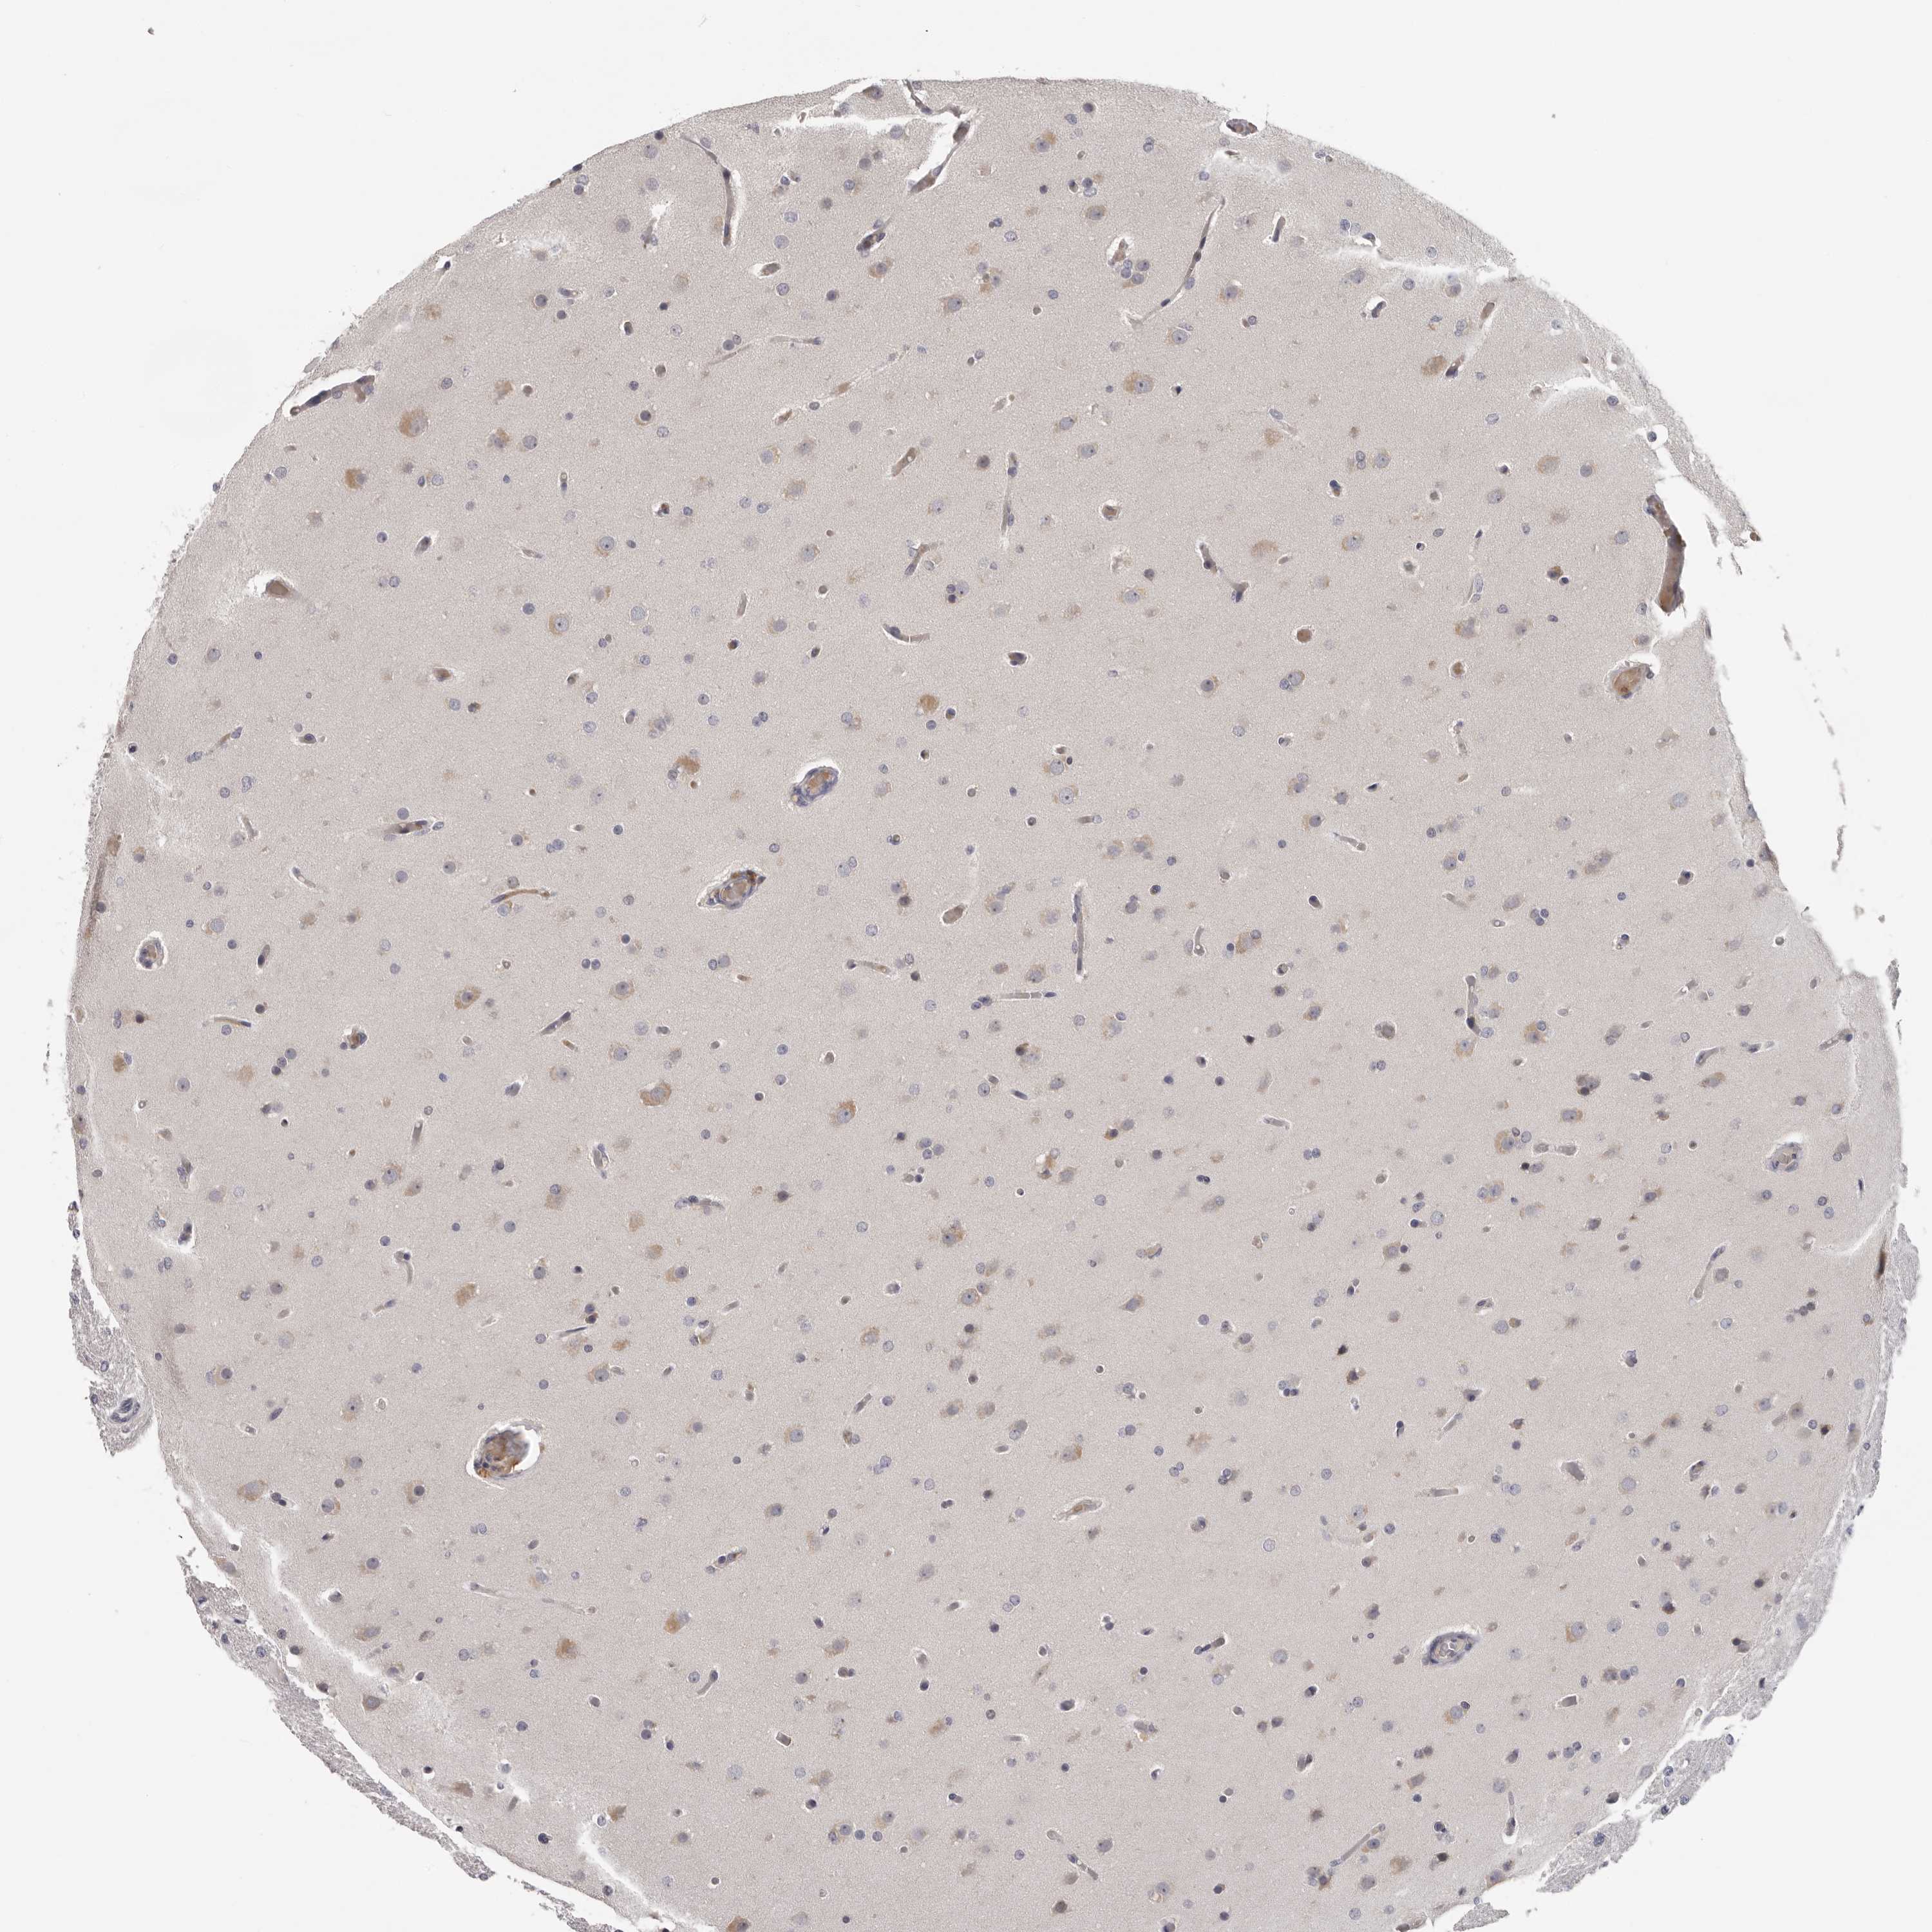

GLIOMA - Protein expressioni

A mouse-over function shows sample information and annotation data. Click on an image to view it in a full screen mode. Samples can be filtered based on level of antibody staining by selecting one or several of the following categories: high, medium, low and not detected. The assay and annotation is described here.

Note that samples used for immunohistochemistry by the Human Protein Atlas do not correspond to samples in the TCGA dataset.

Antibody stainingi

Antibody staining in the annotated cell types in the current human tissue is reported as not detected, low, medium, or high, based on conventional immunohistochemistry profiling in selected tissues. This score is based on the combination of the staining intensity and fraction of stained cells.

Each image is clickable and will lead to virtual microscopy that enables deeper exploration of all samples and also displays staining intensity scores, fraction scores and subcellular localization as well as patient and tissue information for each sample.

Antibody HPA023081

Antibody HPA023103

Antibody HPA024795

Glioma, malignant, High grade

Glioma, malignant, Low grade